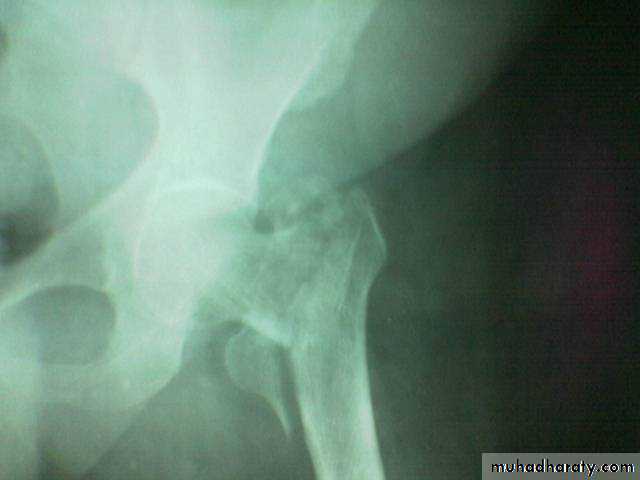

Inter-trochanteric fractures (extracapsular fracture)

.It is extra capsular fracture occurs in elderly..Unite quite easily and seldom cause a vascular necrosis.

The crack runs up between the lesser and greater trochanter.

Pathological anatomy divided into:

Stable:Unstable are those where

a. posteriomedial cortex is shattered.b. poor contact between fracture segment.

Radiological examination

2 typesStable.

Unstable.